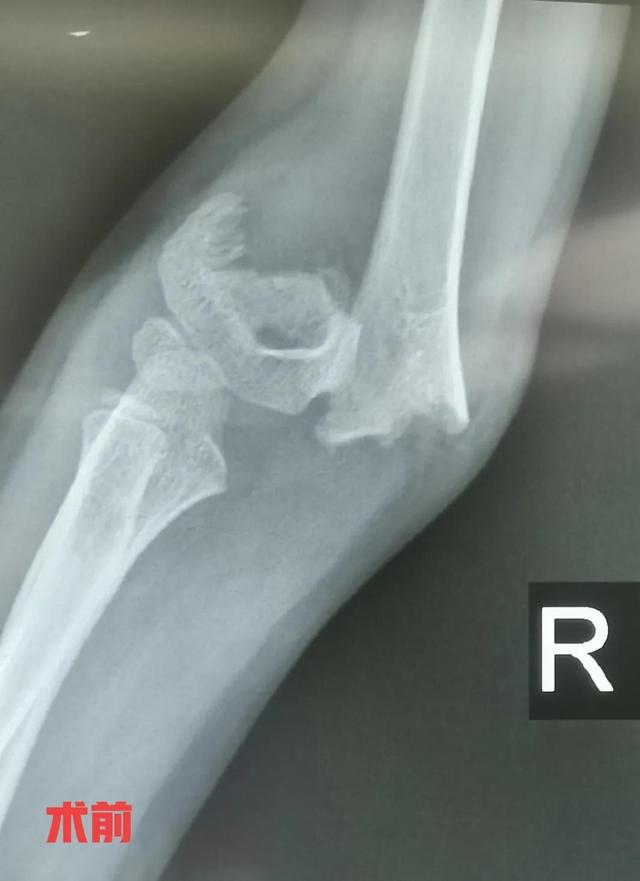

肱骨髁上骨折一般是指肱骨内、外髁上2cm范围内的骨折,在小儿骨折中非常常见的一种骨折,多见于3到12岁的小孩,在小儿肘关节骨折中占比达到80%以上。该骨折可合并血管,神经的损伤,处理不当可引起缺血性肌挛缩,骨化肌炎,肘关节内外翻畸形等。对于非移位骨折或者不完全性骨折单纯石膏托外固定就可以。对于有明显移位的骨折,以前通常都是通过闭合手法复位加石膏托外固定,由于骨折端难以复位,或者骨折端的不稳定性,患肢消肿,石膏托松紧度改变,容易导致骨折复位丢失,甚至骨折复位失效,骨折再次移位,再次复位效果欠佳,反复调节增加小儿痛苦等。目前逐渐倾向于手术治疗,主要采用手法闭合复位克氏针内固定,辅助石膏托外固定,是一种零切开的微创手术,患儿家长容易接受的一种术式。没有特殊情况,基本上手术当天或者术后第一天就可以出院。

病例 女性,7岁,跌伤,右肱骨髁上骨折